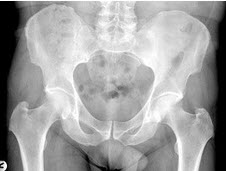

75、单项选择题

女,根据其正常骨盆影像图像,判断其最可能的年龄()

A.69岁左右

B.59岁左右

C.49岁左右

D.19岁左右

E.39岁左右